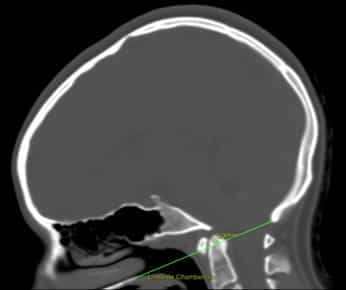

Рисунок 1. Базиллярная импрессия. КТ головного мозга с линией Чемберлена, которая соединяет заднюю стенку большого затылочного отверстия с передней стенкой твердого нёба и должна проходить по верхней части атланта. В данном случае атлант превышает границу на 5,3 мм.

Диагноз ставится при помощи измерения линии Чемберлена и/или других показателей (см. Рис.1).

Прицельная рентгенография черепа в области краниовертебрального перехода и рентгенография позвоночника в шейном отделе проводятся в прямой (фасной) и боковой (профильной) проекциях. Базилярная импрессия диагностируется по увеличению угла между пластинкой основной кости и скатом больше 130°, а также по смещению вверх отростка второго шейного позвонка. Определение местоположения отростка производят по отношению к условным линиям: линии Чемберлена (между задним краем твердого неба и задним краем большого затылочного отверстия) и линии де ля Пти (между верхушками правого и левого сосцевидных отростков). В норме отросток второго шейного позвонка находиться ниже этих линий. Базилярная импрессия характеризуется смещением отростка на 6-30 мм выше линии Чемберлена и на 10-15 мм выше линии де ля Пти.